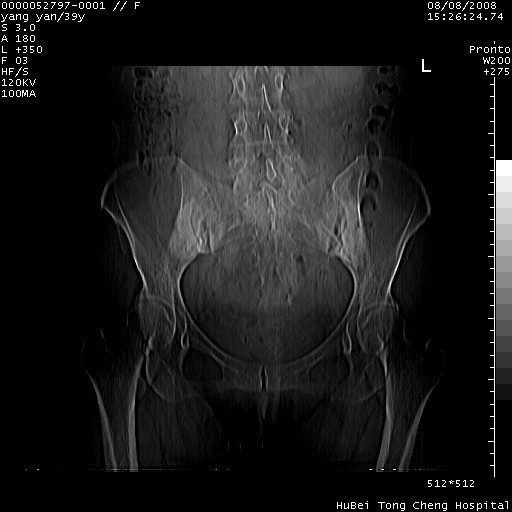

患者 女,39岁。因外伤检查,偶然发现。

典型!双侧骶髂关节致密性骨炎。

典型!病变主要累及双侧髂骨。常见于育龄期妇女。

致密性骨炎,一般不跨越关节面,可是这个骶骨关节面也有硬化。

髂骨致密性骨炎系一种以骨质硬化为特点的非特异性炎症,有高度致密的骨硬化现象,尤其以髂骨下2/3更为明显,但关节间隙则无改变。因位于骶髂关节,且该关节症状明显,故又称之为“骶髂关节致密性骨炎”。 本病90%以上为中年女性,以妊娠后期、尤其分娩后为多见,亦可见于尿路或女性附件慢性感染后,或盆腔内其他感染。此外,臀骶部的外伤亦可诱发或引起本病。  妊娠、分娩及外伤均可引起骶髂关节韧带的撕裂而易使局部的血供受阻。因此早期局部呈现充血、水肿及渗出增加等,渐而局部出现增生与变性反应,随着胶原纤维的致密化而向硬化演变;血管形成厚壁血管,易闭塞而引起髂骨耳状面处缺血和缺氧,骨质呈现硬化性改变,以致手术时局部出血较少。骶髂关节囊壁显示纤维增生、弹性降低及松动样改变。继发于盆腔内炎症者亦出现相类似的病理改变,可能系细菌内毒素作用所致。